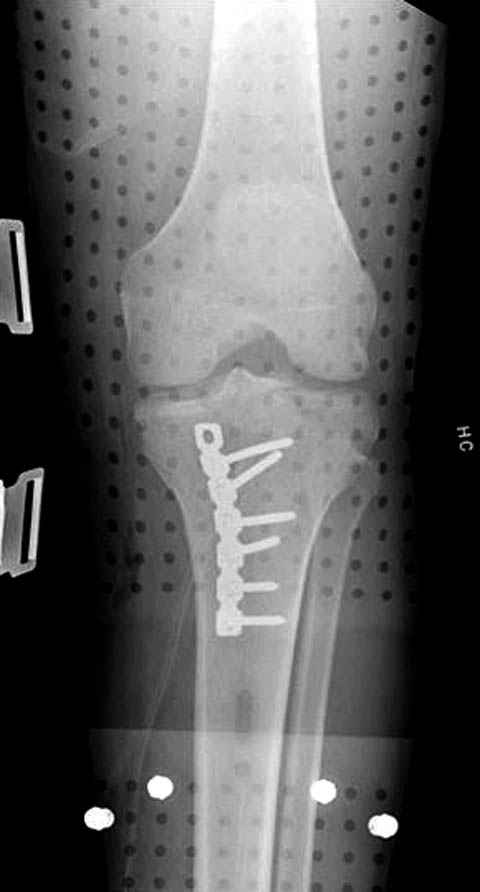

Пациенту сделали КТ - ухитрились сделать на шине Белера (не давал положить прямую ногу) - срезали передний отдел. Планируется на пятницу (24.12) на операцию - синтез длинной мыщелковой LCP-пластиной Synthes :). Отек ближе к слову умеренный (окружность голени +4 см по сравнению со здоровой). КТ и снимок на вытяжении прилагаются.

Уважаемые коллеги! В прошлую пятницу больной прооперирован - как и планировалось мыщелковая LCP от ChM. Малоинвазивно не получилось - один большой доступ :(. (но с минимальным скелетированием б/б кости). Наружный мыщелок собрали, но по контролю видно, что задне-медиальный отдел метаэпифиза смещен. Фиксировать не стали (?). 4-е сутки после операции - по м/тканям без проблем. Дополнительная иммобилизация синтетическим тутором.

P. S. перелом диафиза на контроле не совсем захвачен, но проблем там нет. Приношу извинения за низкое качество Р-грамм - выполнены на сканере (фотоаппарат не работает :)) .

Трудно поверить, что разрекламированная Ортопедическая школа Восточной Украины позволяет такие странные снимки? На прямом снимке сохранен общий контур плато, но не известна судьба импрессии суставной поверхности. На полубоковой?, оставлен без репозиции задне-медиальный отдел, и навряд ли после такой фиксации можно удовлетвориться результатом.

Такая ситуация характерна для многих, когда принимается ошибочное решение, т.е пытаются фиксировать одним имплантом переломы двух мыщелков. Латеральная пластина приемлема только для тех случаев, когда сохраняется интактным медиальный диафизарный кортекс и отсутствует фрагментация на верхушке медиального перелома.

Представленные снимки не информативны, нужны отдельные качественные снимки коленного сустава и голени без ротации.

Надеюсь, представленные снимки разных случаев помогут разобраться в тактике, и критика примется без личной обиды.